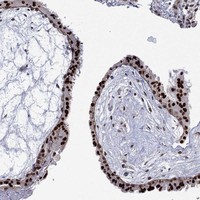

Immunohistochemical staining of human placenta shows strong nuclear positivity in trophoblastic cells.